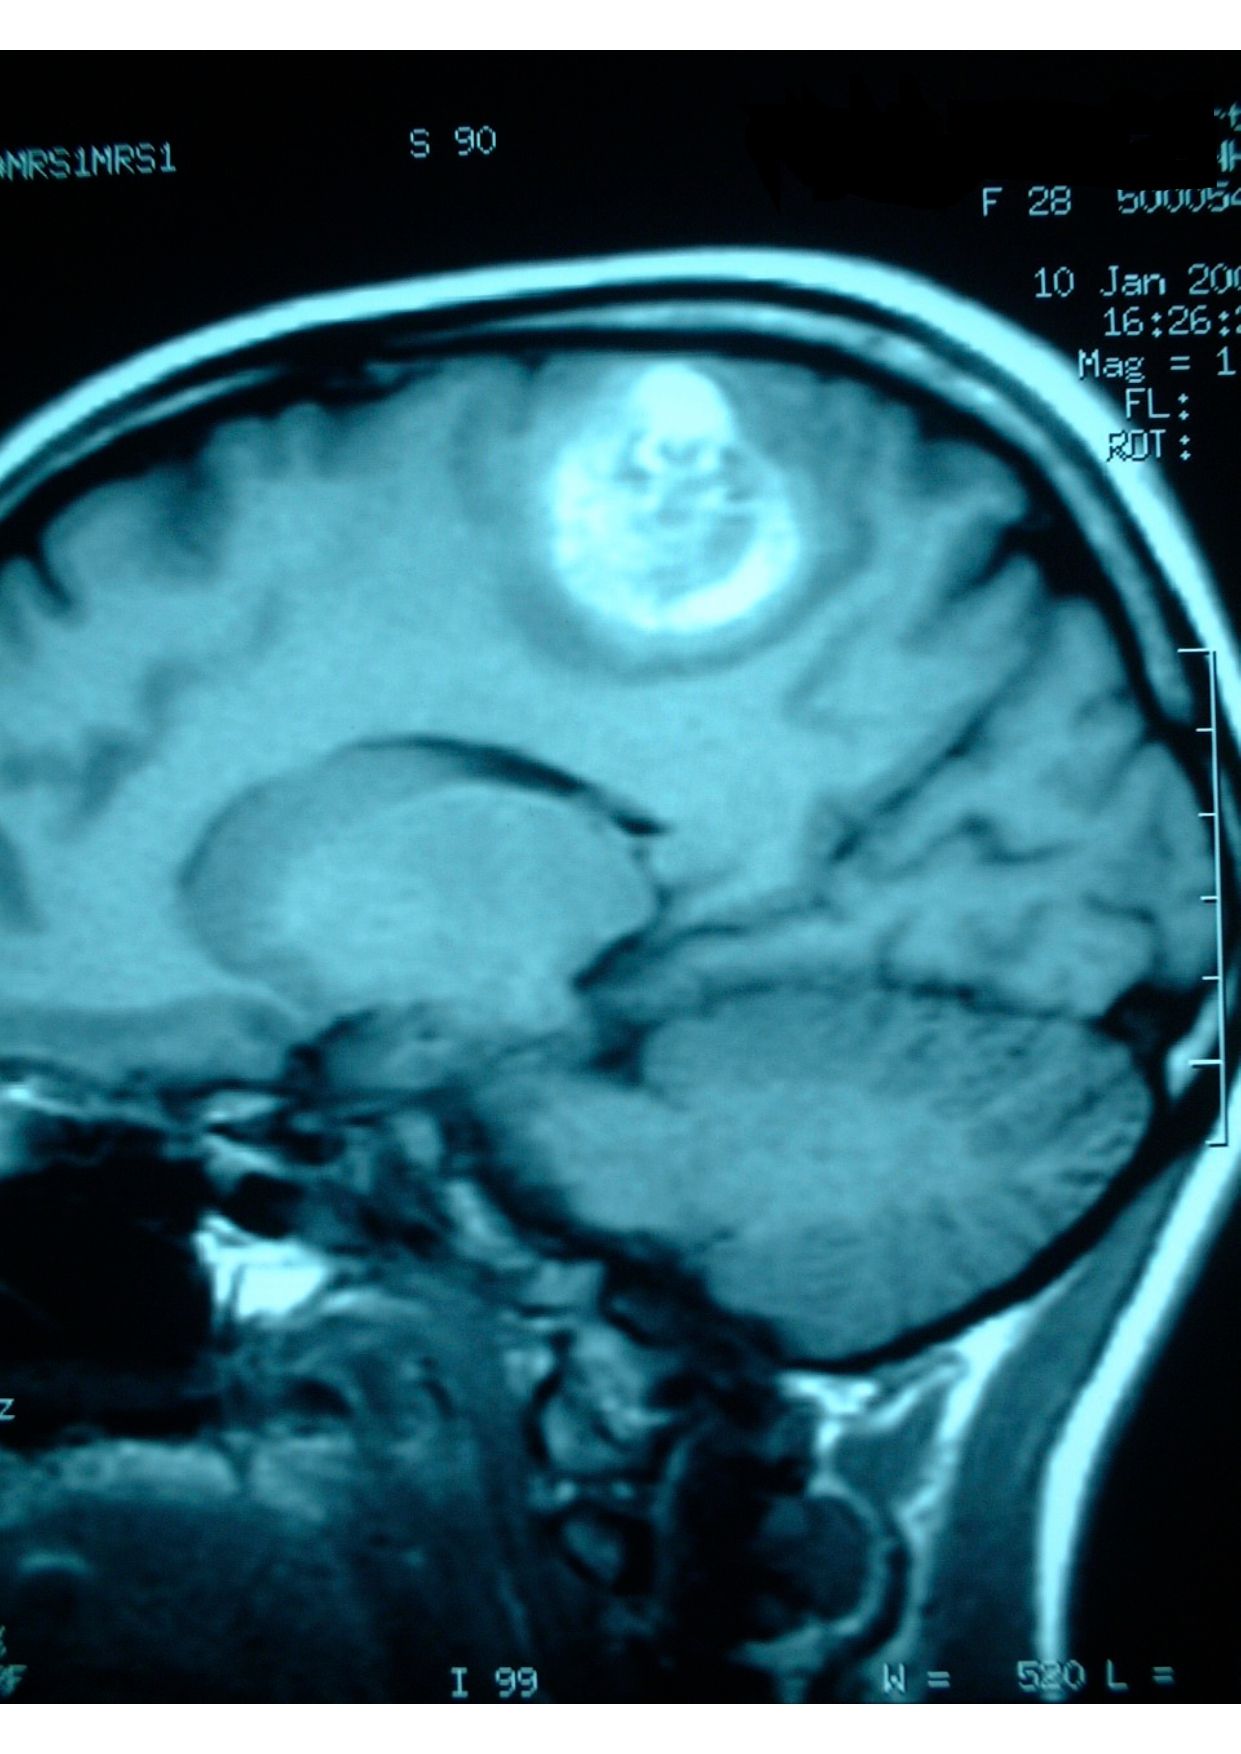

Patologias Tumoral Crânio Encefálica e Raquidiana

- Diagnóstico e tratamento de tumores que afetam o cérebro e a coluna vertebral.

Tumores da Hipófise

- Diagnóstico e tratamento especializado de tumores nesta glândula essencial.